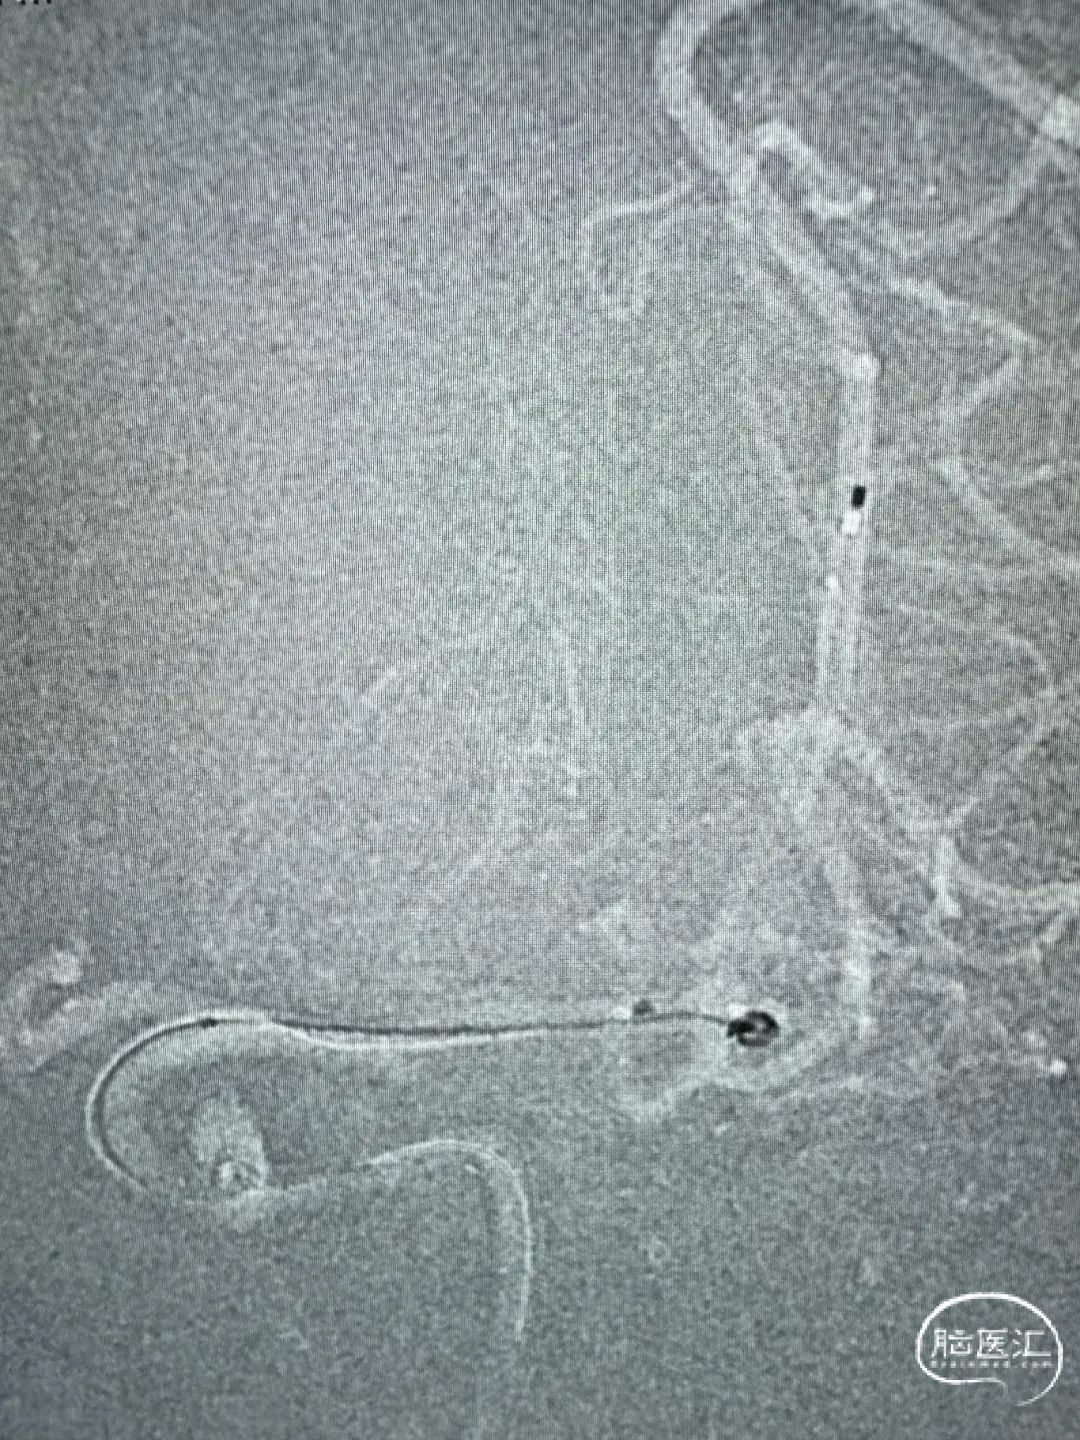

两根Echelon-10分别备用支架及弹簧圈,首圈2.5mm×6cm(ev3)。

Atlas支架3mm×15mm,继续填圈1.5mm×4cm(Galaxy G3 MINI)及1.5mm×4cm(ev3)。

一根Echelon-10备选颞干,另一根Echelon-10送入瘤腔。

首圈1mm×3cm(ev3),最后用1mm×2cm(ev3)收尾。

术后正侧位造影。

动脉瘤完美栓塞,一个支架,两根微导管,一根微导丝主导全程,填塞致密。